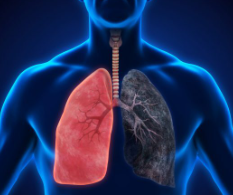

폐암은 국내 암 사망률 1위인 무서운 질병입니다. 특히 흡연자분들이라면 더욱 주의 깊게 살펴보셔야 하는데요. 담배연기 속 유해물질 중 발암물질 함량이 높기 때문에 지속적으로 노출될 경우 폐암 발병 확률이 높아집니다. 하지만 초기에 발견하면 완치율이 높은 편이기 때문에 미리미리 예방해야 합니다. 그래서 오늘은 폐암 초기증상과 예방법에 대해 알아보겠습니다.

폐암은 말 그대로 폐에 생긴 악성종양을 의미합니다. 크게 소세포폐암과 비소세포폐암으로 나뉘는데, 대부분의 폐암환자분들은 비소세포폐암에 해당됩니다. 전체 폐암 중 80~85%가량 차지하며, 편평 상피세포암, 선암, 대세포암등이 속합니다.